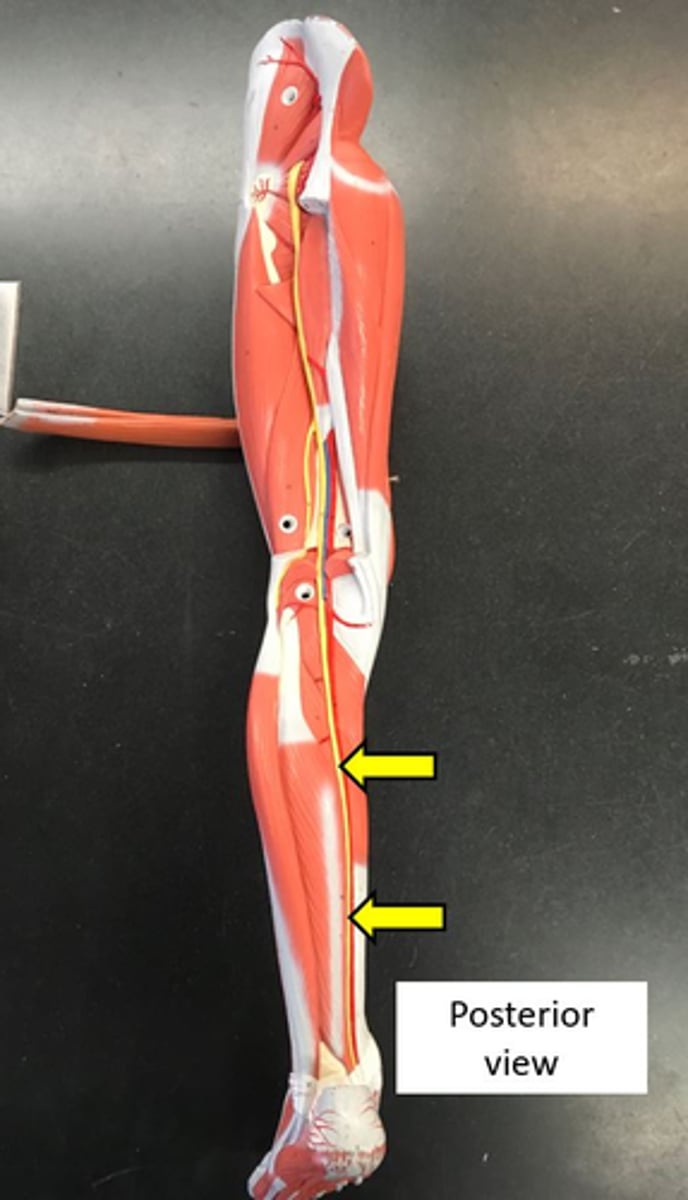

sciatic nerve

common fibular nerve

tibial nerve